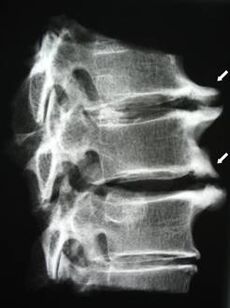

A kezdeti szakaszban az osteochondrosis kimutatása MRI segítségével történik. Később a patológiát radiográfia segítségével lehet diagnosztizálni. A nyaki gerinc röntgenfelvételein észrevehetővé válik a csigolyák közötti távolság csökkenése, a fazett ízületek patológiás változásai és az osteophytosis.